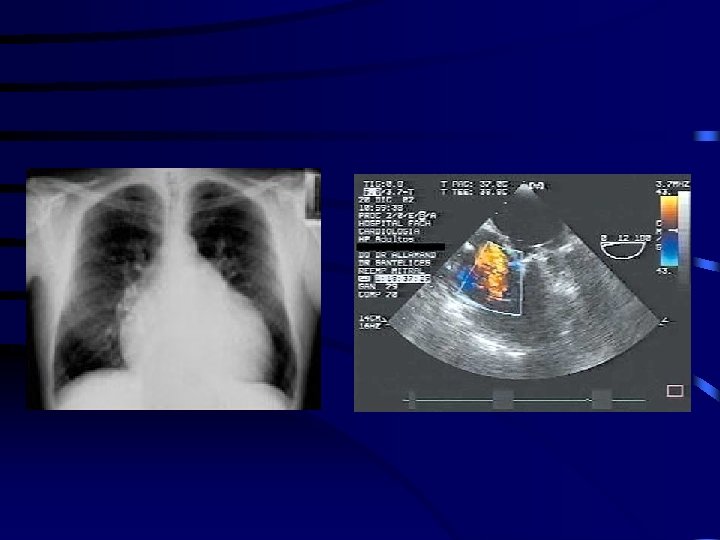

Ecocardiografía 2 D y Doppler transtorácica • Método no invasor más sensible y específico • Utilidad: – Cálculo del gradiente transvalvular y área de orificio mitral – Presencia y gravedad de otras lesiones valvulares acompañantes – Grosor de valvas, distorsión de aparato subvalvular e idoneidad anatómica valvular – Tamaño de cavidades, función de VI, presión en AP Clase I, Nivel de evidencia B

Ecocardiografía VM engrosada, AI Orificio de VM estenosado

Ecocardiografía (A) Ecocardiografía 2 D: densa calcificación de VM (flecha) (B) Ecocardiografía Doppler: muestra gradiente transmitral alto y área valvular disminuida

Diagnostico • EKG: HVI, crecimiento AI, crecimiento VD, evidencia IMA o isquemia • RX TX: crecimiento VI, AI, congestion pulmonar, derrame pleural • Ecocardiograma: Evalua anatomia del ap. v. mitral: – – – Enf reumatica: engrosamiento valvas PVM: valvas voluminosas elongadas ECC: alteraciones motilidad segmentaria Ruptura cuerda tendinea Calcificacion anillo mitral